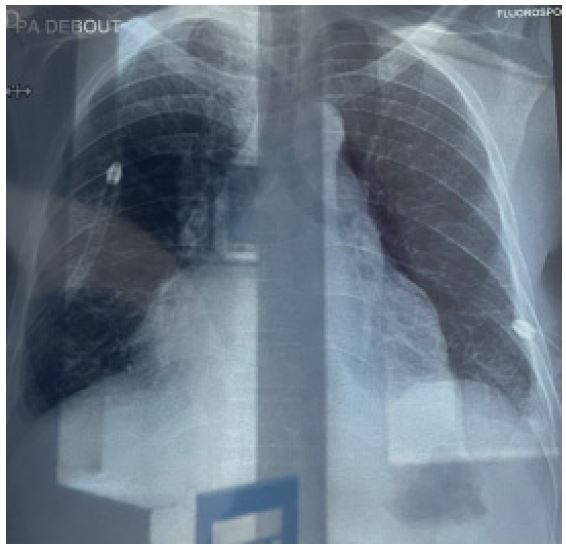

Figure 6: Showing associated bilateral moderate pleural effusion with lung atelectasis.